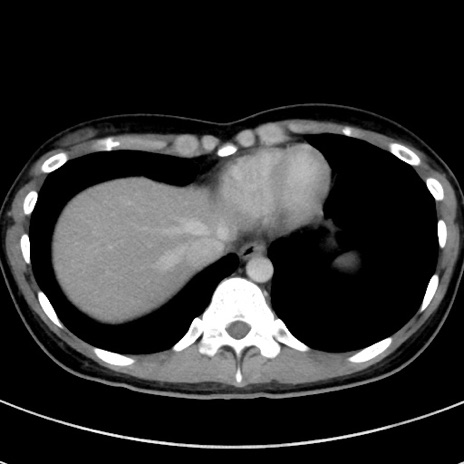

症例17(横断像)

【症例】20歳代女性

【主訴】嘔吐、下腹部痛

【現病歴】昨日夕食後に嘔吐し下腹部痛が出現。本日になっても嘔吐持続し改善しないため来院。

【身体所見】意識清明、BT 37.2℃、BP 108/67mmHg、腹部:平坦、やや硬、下腹部正中から右にかけて圧痛あり、反跳痛軽度あり、tapping pain(+)。

【データ】WBC 13600、CRP 14.94